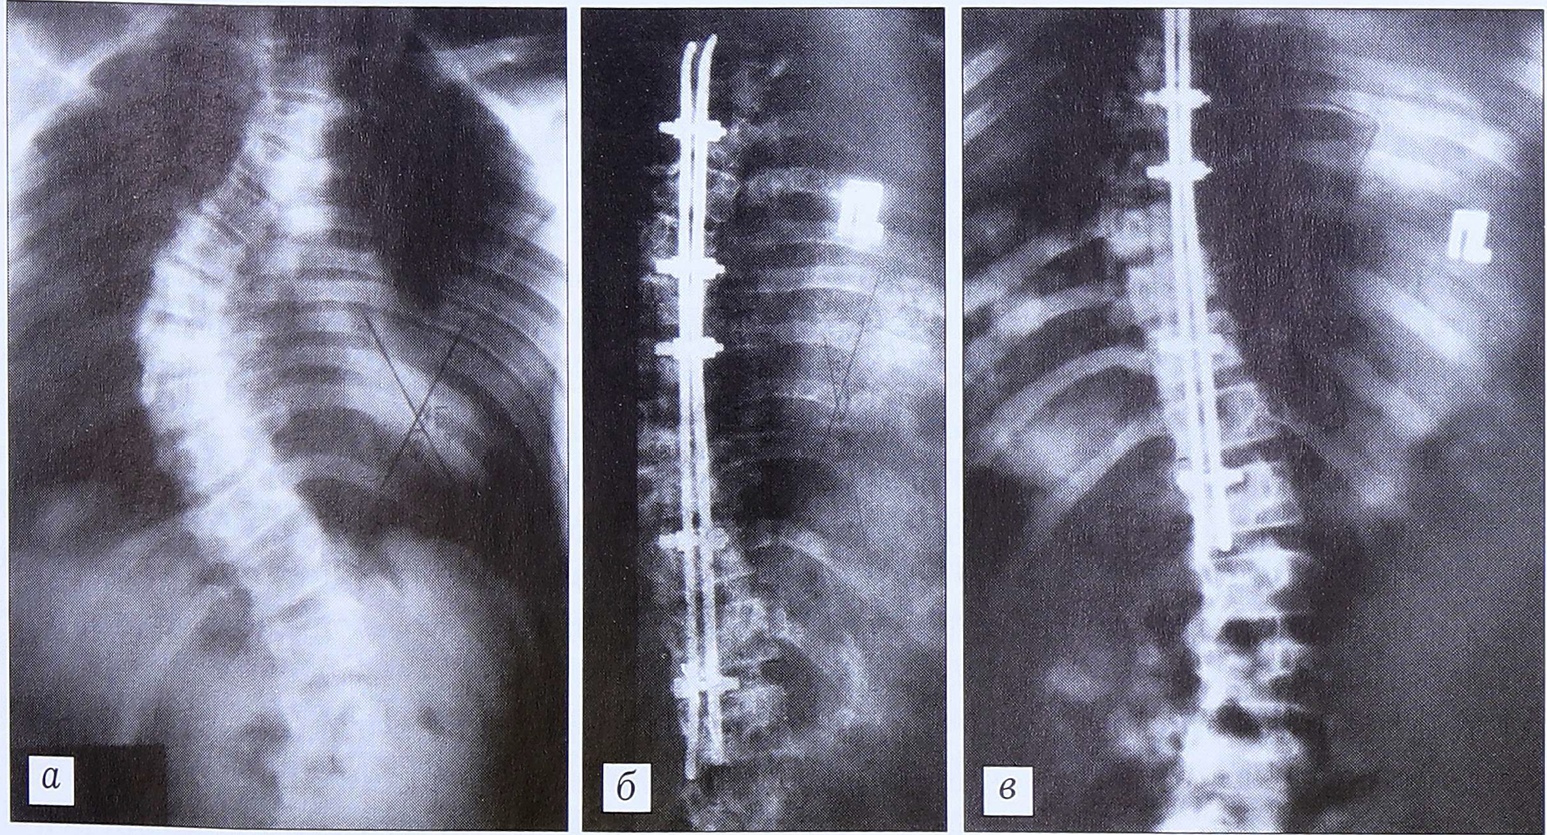

У 18 больных (подгруппа 1в) коррекция сколиотической дуги осуществлялась дистракторами Харрингтона. Мы несколько модифицировали процесс установки крючков дистрактора с тем, чтобы предотвратить их самопроизвольный выход из своего ложа под дугами позвонков (наблюдавшийся ранее в нескольких случаях). Крючки устанавливаем под дуги с переходом частично под основания остистых отростков, приближая их к оси вращения позвонка, для чего производим краевую резекцию дуги и основания остистого отростка сопредельных позвонков. После такой модификации при проведении 23 операций с применением дистрактора Харрингтона вывихиваний или других смещений крючков мы не наблюдали ни в одном случае.

У больных, оперированных с применением только дистрактора Харрингтона (подгруппа 1в), достигнутая коррекция составляла от 28 до 45°. В послеоперационном периоде эти больные до 15 мес носили различные корсеты, занимались лечебной гимнастикой. Потеря коррекции составила у них 40-45%.

У пациентов контрольной группы коррекция деформации производилась дистрактором Харрингтона. У 10 из них была использована поперечная тяга к дистрактору Харрингтона от вершины основной дуги массивными кортикальными трансплантатами. Достигнутая коррекция в контрольной группе составила от 22 до 45°. Потеря коррекции колебалась от 35 до 65%. Значимого улучшения результатов при применении боковой тяги к дистрактору мы не отметили. В то же время у 5 больных выявлено несколько более выраженное нарастание торсии и ротации позвонков на вершине деформации, что мы связываем с односторонним давлением на остистые отростки с выпуклой стороны, совпадающим с вектором ротирующих позвонки сил. Незначительное уменьшение темпов потери фронтальной коррекции у этих больных, возможно, было обусловлено созданием массивного костного блока за счет крупных кортикальных аутоили аллотрансплантатов. Большие объемы потери коррекции в контрольной группе можно объяснить и тем, что пациенты этой группы проходили значительно более короткое послеоперационное лечение, ограничивавшееся ношением фиксирующих корсетов в течение 6-8 мес.